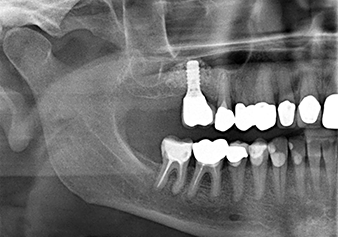

Dopo un controllo intermedio (Fig. 4) è stata eseguita un'ulteriore fase di preparazione (Fig. 5). Lo strumento idraulico Z35P è stato utilizzato in un secondo momento per sollevare la membrana sino alla posizione desiderata (Fig. 6 e 7). In seguito alla suddetta operazione, si è proceduto ad una ulteriore preparazione piezochirurgica della sede dell'impianto conclusasi con l'applicazione della fresa e della fresa a spallamento sul diametro dell'impianto di 4,8 mm. Il materiale di rinforzo (dimensione delle particelle di ca. 0,8 - 1,6 mm) è stato introdotto sotto la membrana di Schneider prima che venisse inserito l'impianto (Fig. 8).